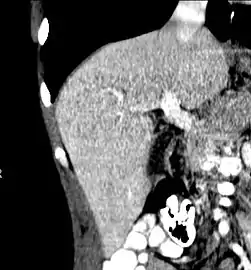

Axial CT image showing anomalous hepatic veins coursing on the liver's subcapsular anterior surface[70]

Maximum intensity projection (MIP) CT image as viewed anteriorly showing the anomalous hepatic veins coursing on the anterior surface of the liver

Lateral MIP view in the same patient as previous image

A CT scan in which the liver and portal vein are shown